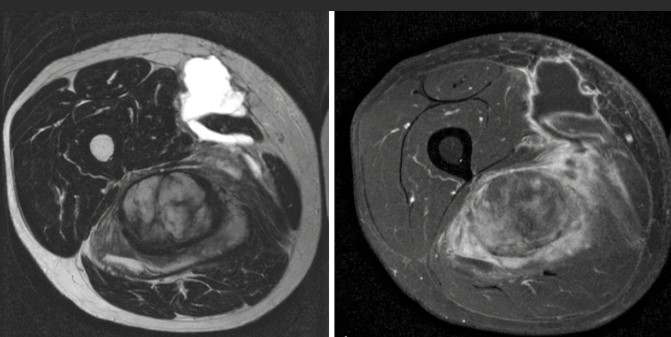

Die Magnetresonanztomographie des Beckens, kurz MRT Becken genannt, ermöglicht es den Bereich des Beckens bildlich darzustellen. Hierbei ist nicht nur der knöcherne Teil des Beckens zu sehen, sondern auch Gelenke und insbesondere Organe, die sich im Beckenbereich befinden. Die MRT Becken ermöglicht strahlenfreie und präzise Bildgebung.

Bei der Magnetresonanztomographie, kurz MRT, handelt es sich um eine bildgebende Untersuchung, bei der die Strukturen des Beckens und der darin befindlichen Organe ohne Strahlung dargestellt werden können. Im Gegensatz zum herkömmlichem Röntgen und der Computertomographie werden bei der MRT starke Magnetfelder und Radiowellen zur Aufnahme der Bilder verwendet. Darüber hinaus ermöglicht dies sehr detaillierte, hochauflösende Bilder. Die MRT-Untersuchungen sind schmerzfrei und ungefährlich.

Die Magnetresonanztomographie überzeugt durch ihren hohen Weichteilkontrast. Damit eignet sich dieses bildgebende Verfahren ideal zur Beurteilung von Tumoren, Entzündungen und Nekrosen von Knochen, Weichteilen und Organen sowie von Schäden am Kapselbandsystem der Gelenke und inneren Gelenkverletzungen.

Der Körper wird zweidimensional Schicht für Schicht gescannt, wodurch zahlreiche Querschnittsbilder entstehen. Diese werden dann am Computer übereinander geschichtet, sodass ein dreidimensionaler Eindruck entsteht. Auch rechnerisch ist eine exakte 3D-Rekonstruktion möglich, sodass die in der MRT entstandenen Bilder anschließend aus jedem Blickwinkel betrachtet werden können. Anhand dieser MRT Bilder können verschiedenste Strukturen und Funktionen des Beckens und Körperinneren detailliert beurteilt werden.